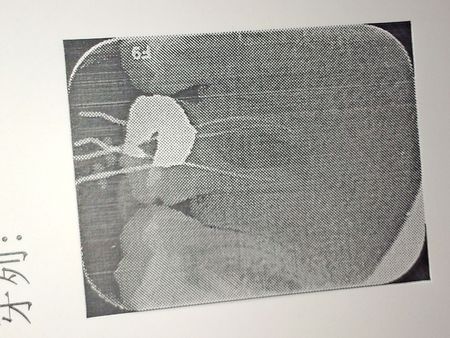

根管治疗侧穿图片